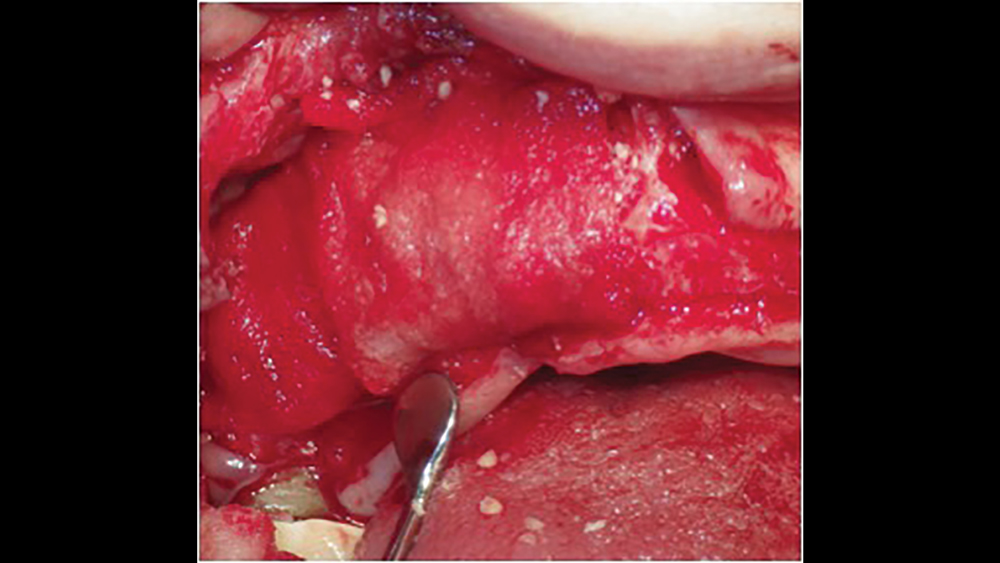

Figure 4b: Mesh exposure

Figures 4a, 4b: Titanium mesh membranes have holes incorporated within the mesh (4a), which allow for maintaining blood supply; however, these membranes have the disadvantage of increased wound dehiscence, which commonly involves exposure of the mesh (4b).